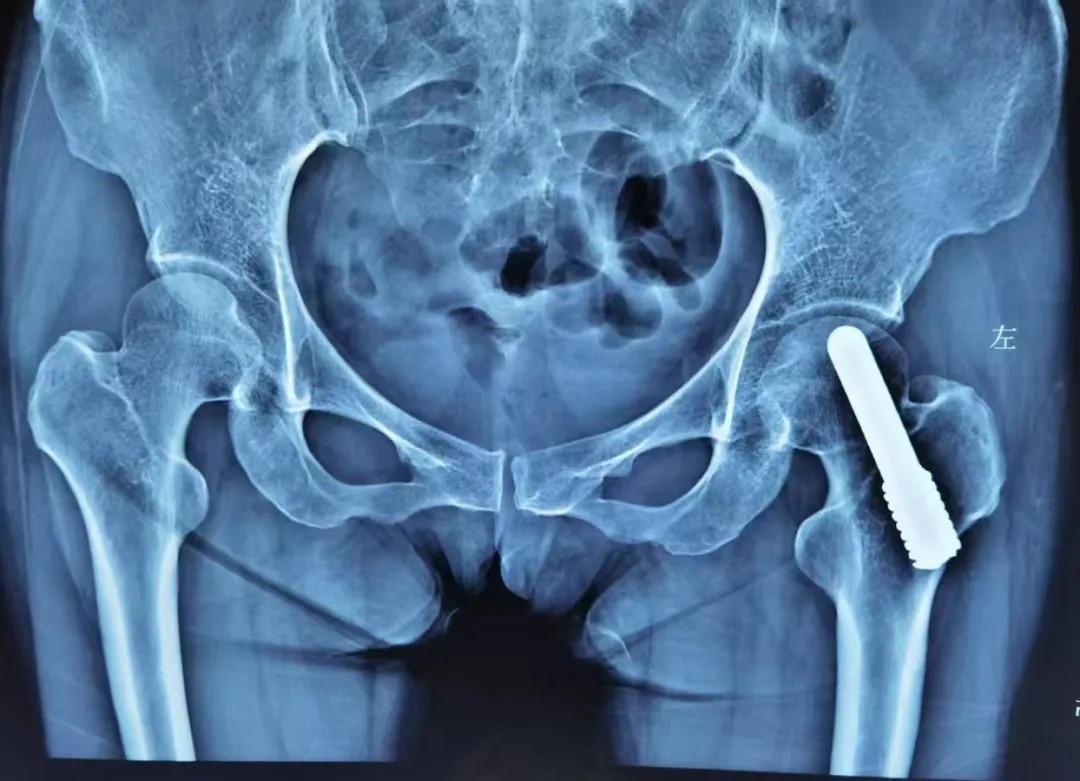

中期:微创 “救” 股骨头

股骨头坏死中期,此时股骨头开始出现小裂缝但没塌陷,可以做微创保髋手术,比如 “髓芯减压术”(钻小孔减轻股骨头内压力)、“植骨术”(填入新骨促进修复),术后配合康复训练,尽可能保留股骨头功能。

若股骨头塌陷轻微,还能尝试 “截骨术”(调整股骨头受力位置);或采取钽棒置入术,即在股骨头中放入钽棒,支撑坏死区域。